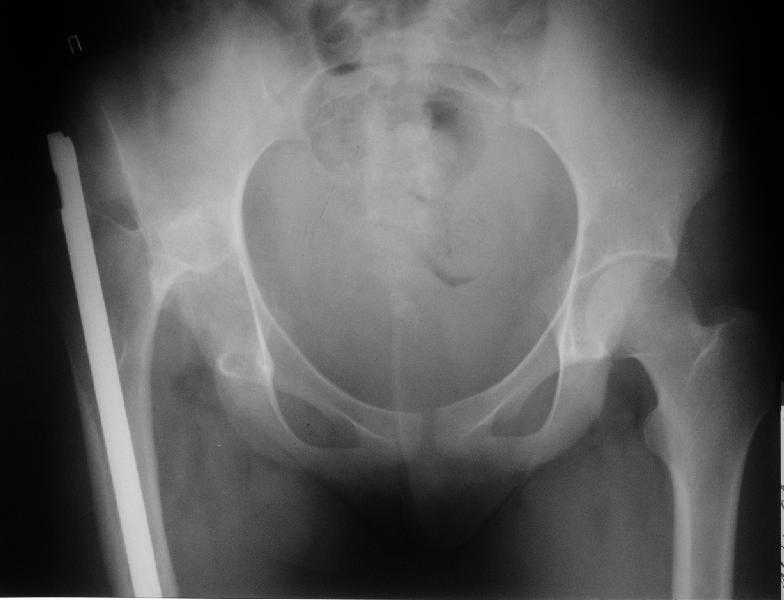

Здравствуйте уважаемые коллеги.Больная 18 лет. Травма 12.08.2007. Лечилась в одном из городов Свердловской области.

15.08.2007 в ЦРБ сделан открытый остеосинтез правого бедра интрамедуллярным стержнем, после чего была наложена гипсовая кокситная повязка и пациентка лечилась амбулаторно в течение 1,5 месяцев. На контрольном Rn исследовании в марте 2008 диагностирован подвздошный вывих правого бедра.